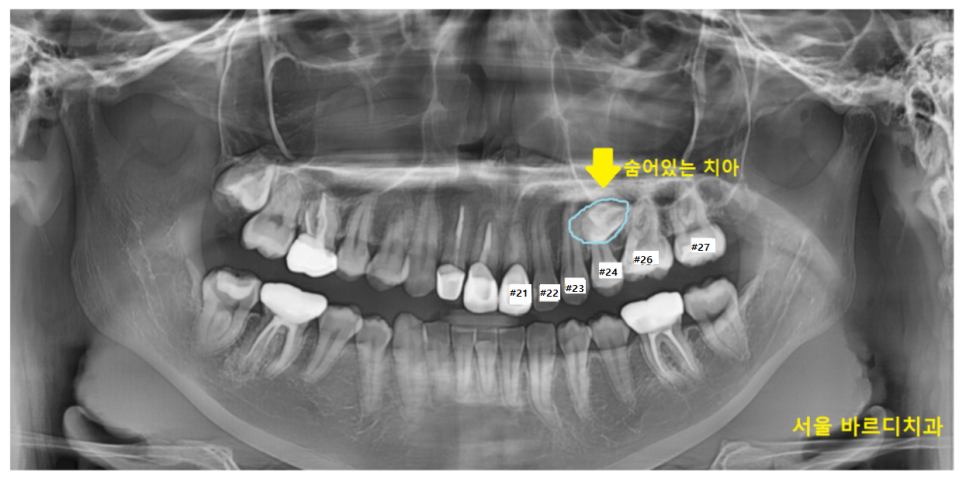

23.07.01

나와야할 영구치가

잇몸 안에 묻혀서

나와있지를 않네요~

완전히 묻혀있다 하여

완전 매복치라고 표현합니다.

교정 진단을 위해 촬영한 사진에서도

숨어있는 매복치 보이시죠~?